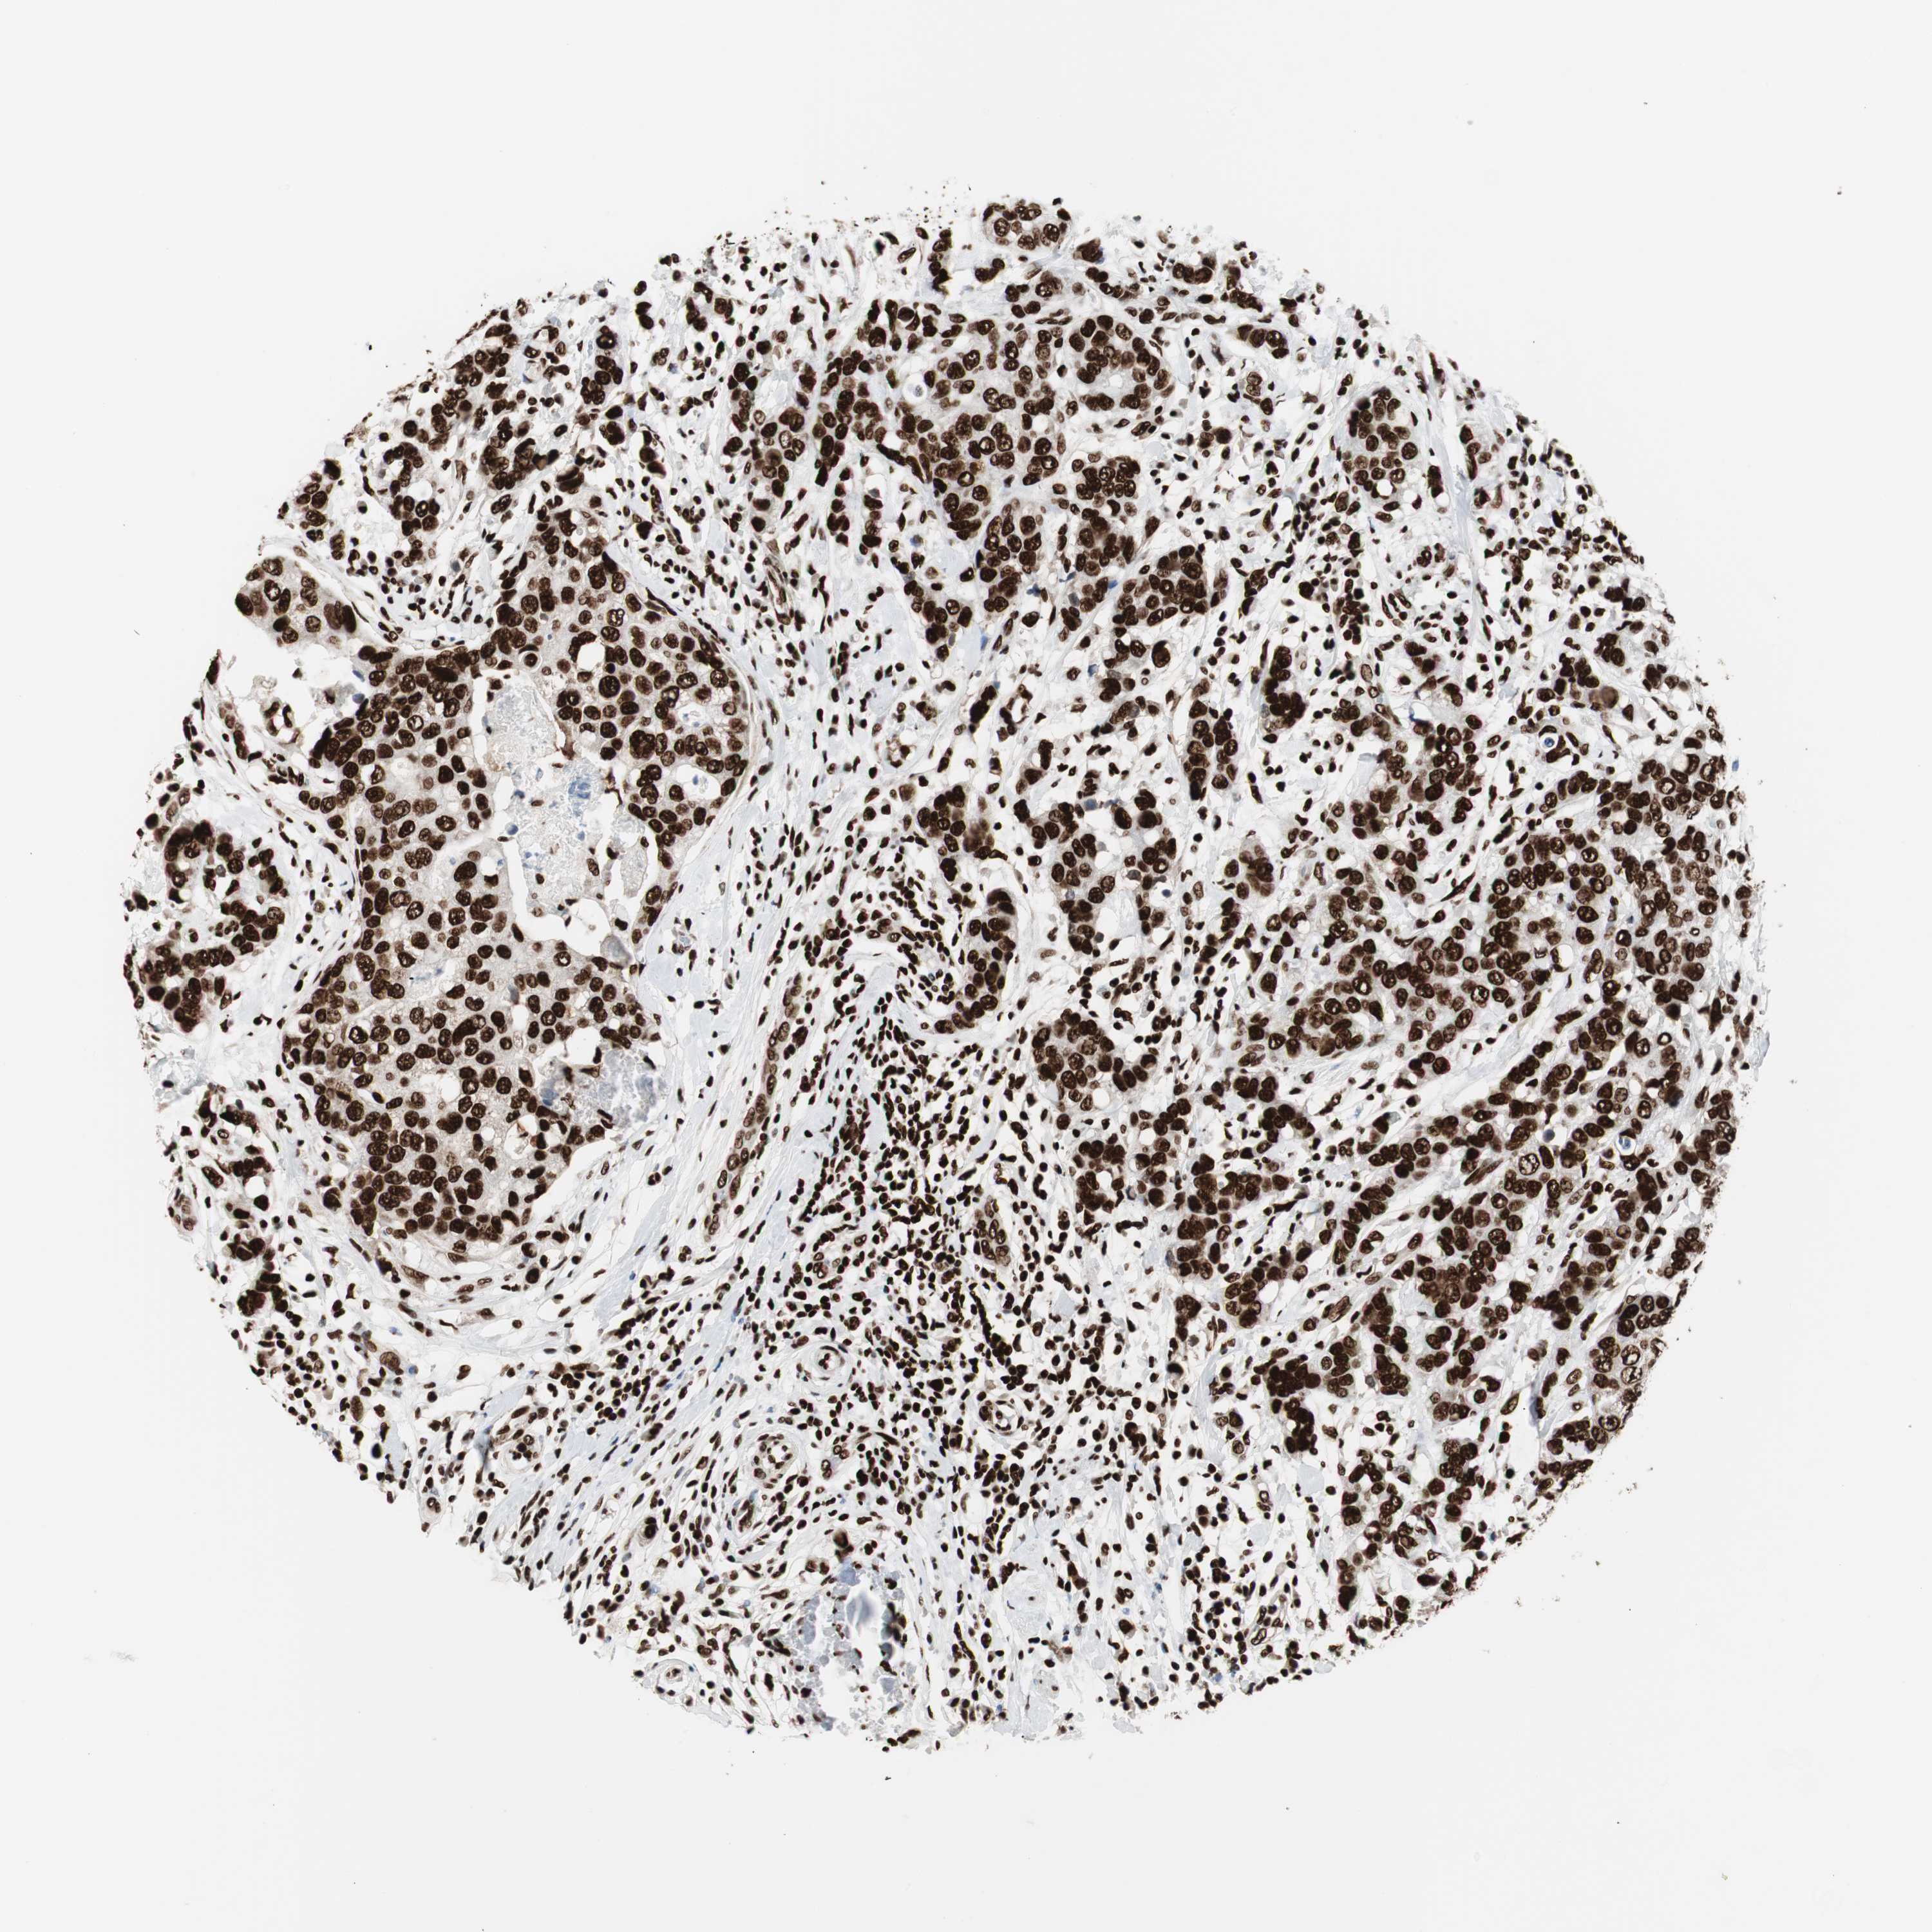

BRCA TCGA BRCA VALIDATION PROTEIN EXPRESSION